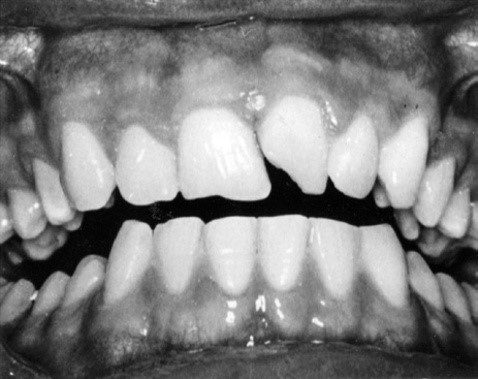

Gãy men và gãy men-ngà không liên quan đến tủy xảy ra thường xuyên ở cả răng sữa và răng vĩnh viễn. Chúng thường chỉ giới hạn ở một răng duy nhất, thường là các răng cửa giữa hàm trên. đặc biệt là các góc gần hoặc xa (Hình 13.3).

Đường gãy có thể nằm ngang theo chiều gần xa. Đôi khi chỉ liên quan đến thùy giữa của rìa cắn (Hình 13.4).